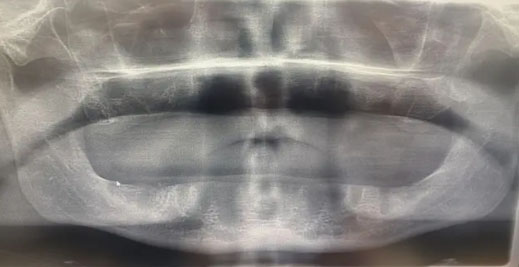

Στην πρώτη συνεδρία αφαιρέθηκαν τα φυσικά δόντια και τοποθετήθηκαν 14 εμφυτεύματα με προσωρινές προσθετικές. Ο Ντέντον περιγράφει έντονο πόνο και επιδείνωση της κατάστασης τις επόμενες εβδομάδες.

Τα προσωρινά αποκολλήθηκαν και σε δεύτερη επίσκεψη τον Μάρτιο αντί για διόρθωση διαπίστωσε ότι είχαν αφαιρεθεί όλα τα εμφυτεύματα. Επέστρεψε στη Βρετανία χωρίς δόντια.

Ιατρικοί έλεγχοι στο Ηνωμένο Βασίλειο έδειξαν σοβαρή λοίμωξη των ούλων. Οι οδοντίατροι εκτίμησαν ότι η οστική δομή δεν ήταν ικανή για τα αρχικά εμφυτεύματα.